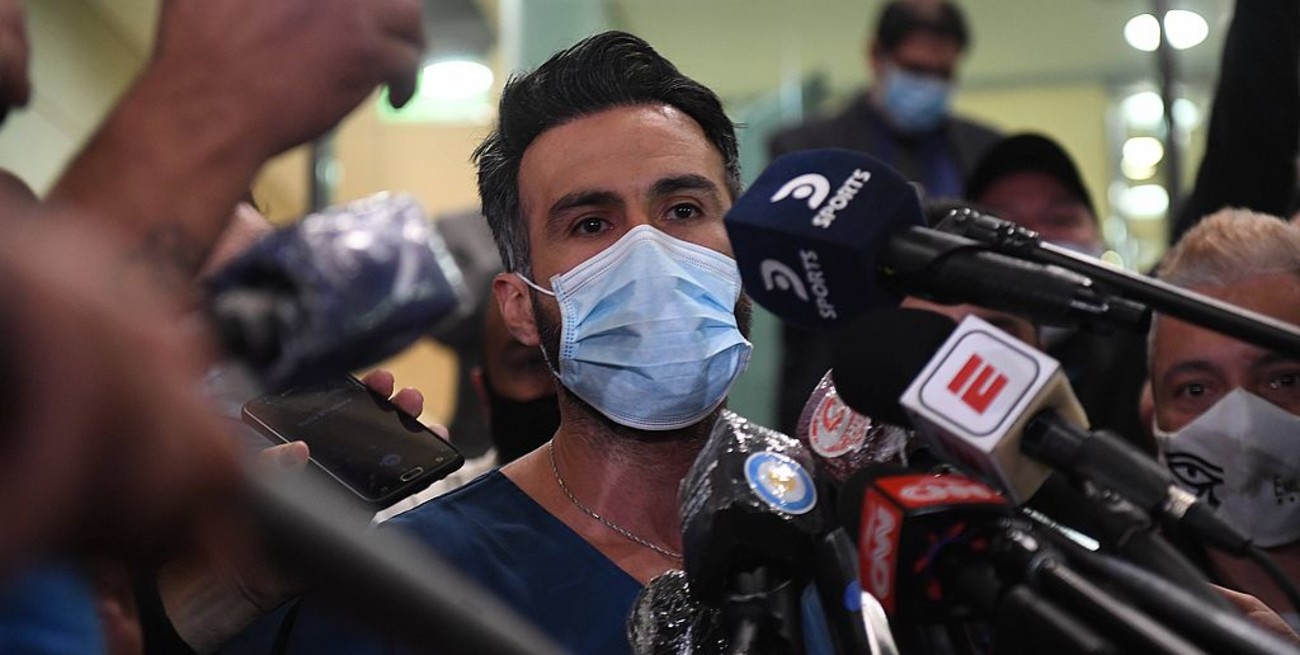

La recuperación de Diego Maradona tras la operación de un hematoma subdural que se le practicó este martes por la en la Clínica Olivos "es buenísima", aseguró este miércoles por la tarde su médico personal, Leopoldo Luque, en las puertas del centro de salud donde el astro futbolístico se encuentra internado en terapia intensiva.

"La recuperación de Maradona es buenísima", aseguró Leopoldo Luque

"Maradona no tiene ningún compromiso neurológico. La recuperación es buenísima. 'Vos quedaste como un campeón', me dijo. Ahora está bajo un control de terapia intensiva y la familia lo está cuidando", explicó Luque a todos los medios de prensa convocados en el acceso a la Clínica Olivos.

"Nosotros hoy no nos planteamos el Covid-19 como un condicionante para definir el alta. Acá es el día a día y de verlo hoy a la mañana a lo que observamos ahora, es una gran alegría comprobar lo bien que está", destacó.

Luque, quien llegó a la clínica a bordo de una moto y allí fue rodeado por un buen número de hinchas de Gimnasia y Esgrima que viajaron por la mañana desde La Plata "para hacerle el aguante a nuestro entrenador", según dijeron.

"Diego está cursando un posoperatorio y esto es estadístico, porque la medicina no es una ciencia exacta. Las 24 o 48 horas posteriores a una intervención quirúrgica son esas en las que surgen las complicaciones, pero eso no sucedió y por eso estamos tan contentos", completó su descontracturado informe Luque, quien, acto seguido, siguió sacándose fotografías con los hinchas "triperos", para los que se convirtió en un nuevo ídolo allende las canchas por haber operado y curado al "otro", a Maradona .